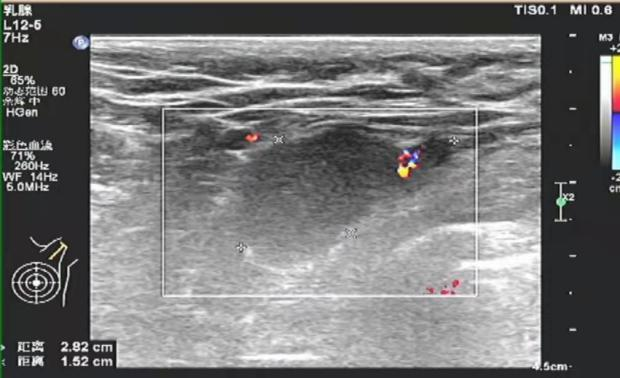

2020-11-06我院行左腋窝淋巴结穿刺活检术,术后病检示:“左腋窝淋巴结”浸润性癌,组织学Ⅲ级

免疫组化结果:ER(中-强+,约80%),PR(强+,约90%),Cerb-B2(3+),Ki67(+,约40%)

图4. 免疫组化PR